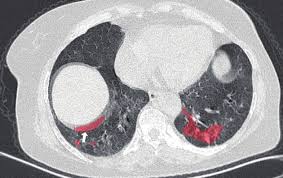

彩神v肺衛(wèi)士 - 肺部疾病智能檢測平臺

查看詳情>>

針對肺結節(jié)、肺炎等肺部疾病的CT影像智能分析,協(xié)助醫(yī)生快速診斷。